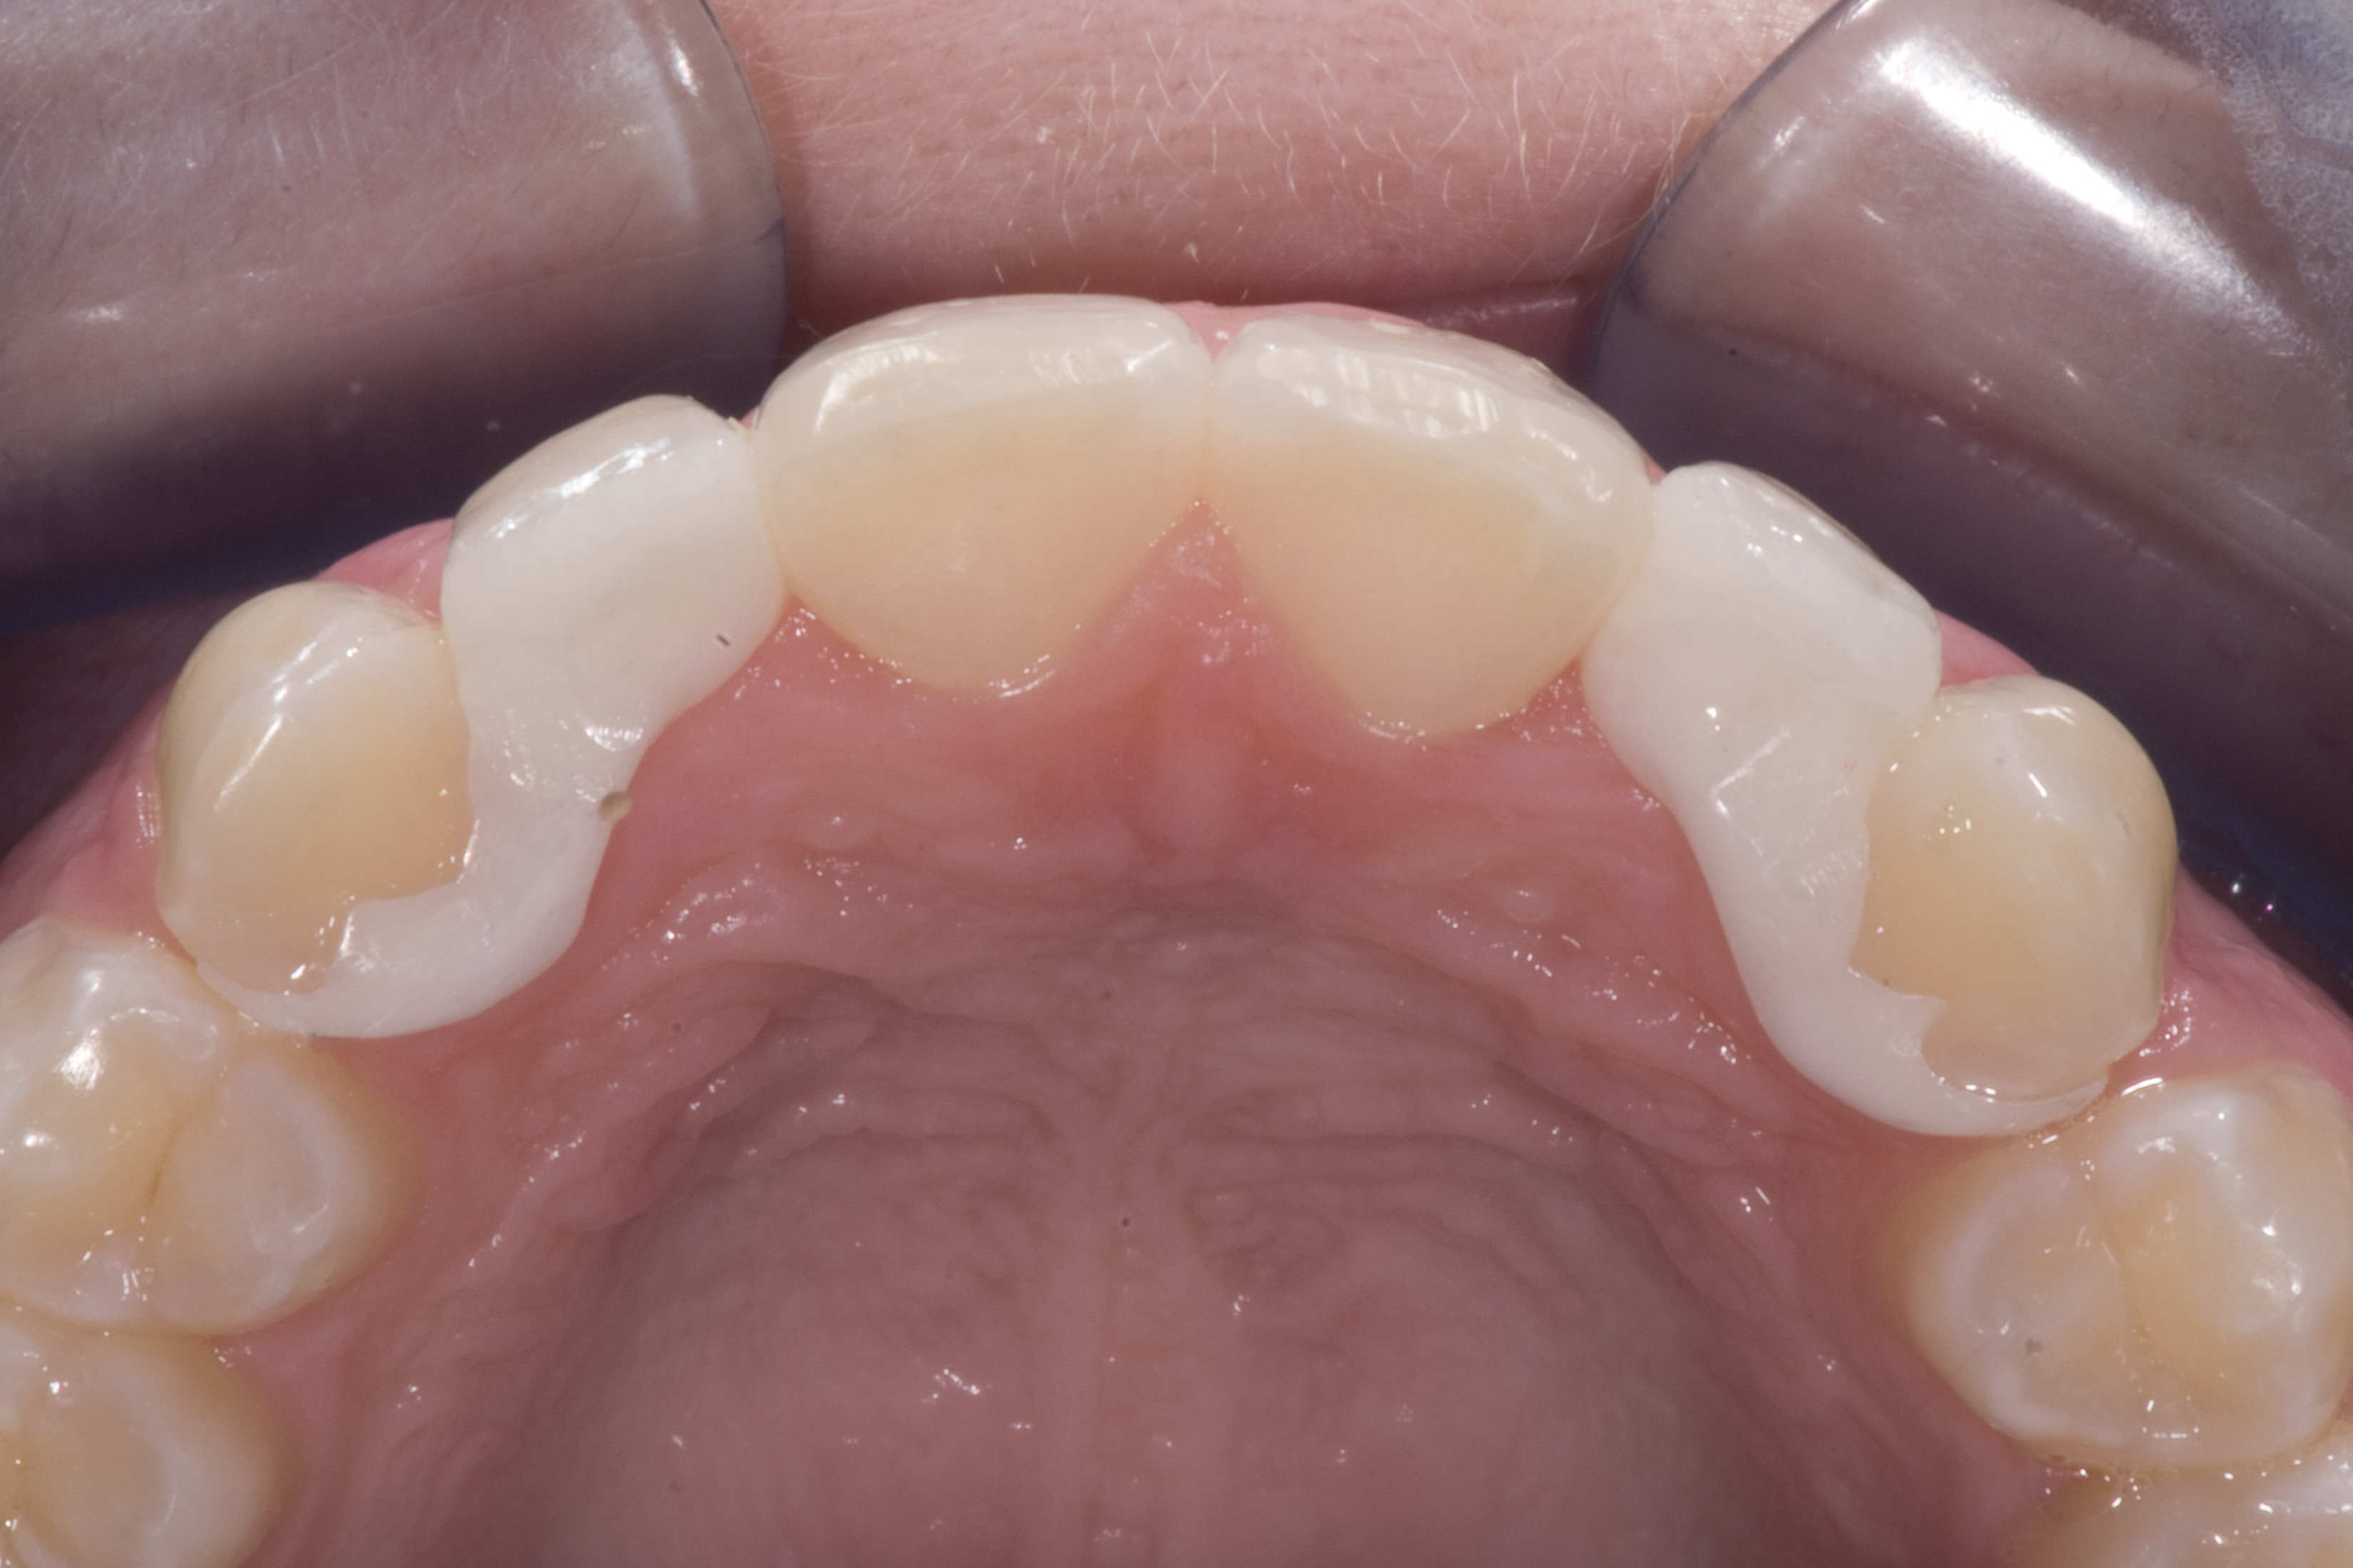

(14.) Occlusal view. Some form of augmentation would be needed if implants were being considered.

Figure 14